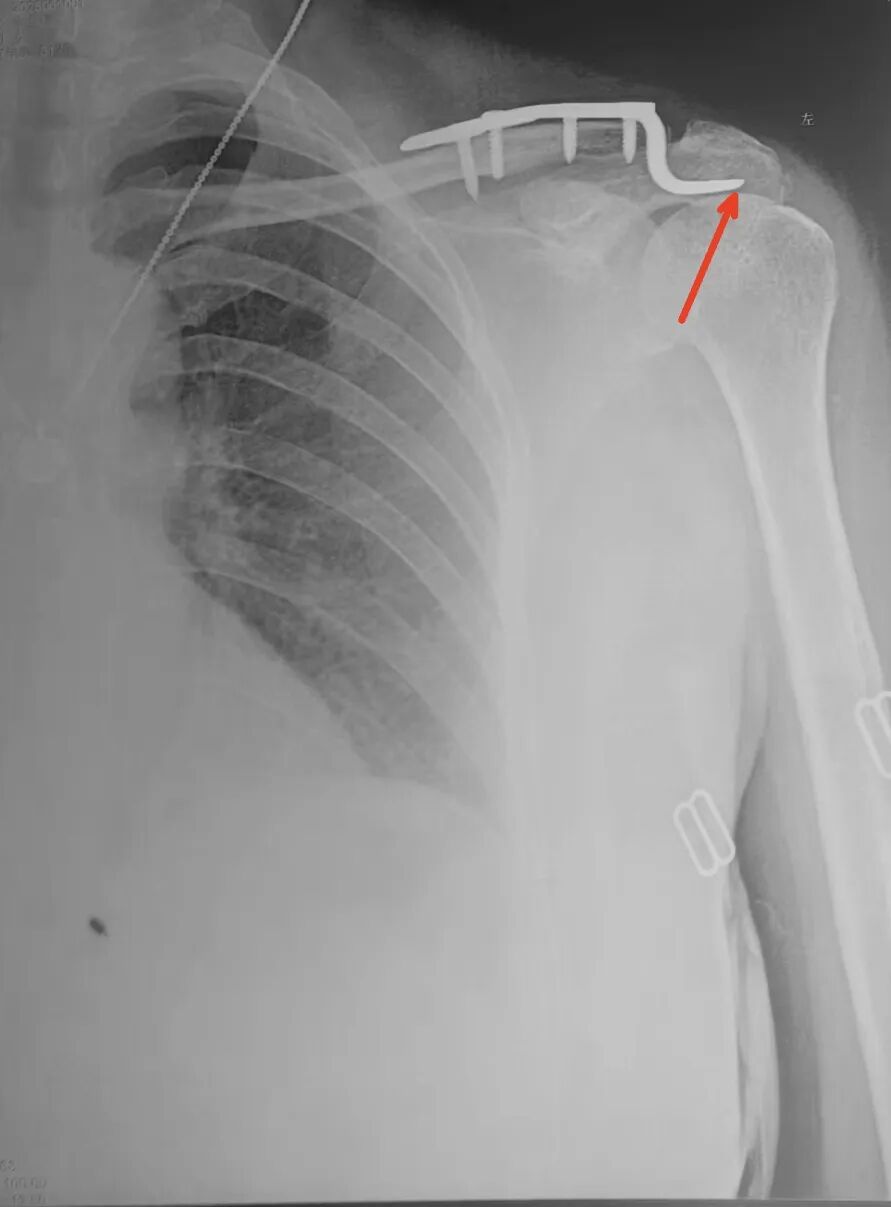

大清早还看到一个患者发的片子

袢板术后2天再脱位

当然和技术和患者依从性关系也很大